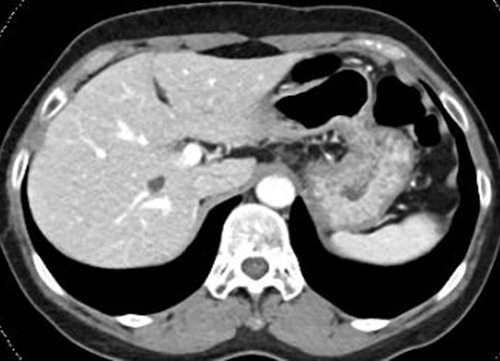

복부 CT는 X-ray(엑스레이)보다 훨씬 정밀한 영상을 찍을 수 있어서, 다양한 장기의 상태를 한눈에 볼 수 있어!

🔹 간 질환 – 지방간, 간경화, 간암 등 확인 가능

🔹 췌장염·췌장암 – 췌장에 염증이 생기거나 종양이 있는지 체크 가능

🎗 간암, 췌장암, 대장암, 신장암 등 초기 단계에서 발견 가능!

🎗 양성종양 or 악성종양(암) 판별 – 혹이 생겼다면 악성인지 양성인지 확인할 수 있음